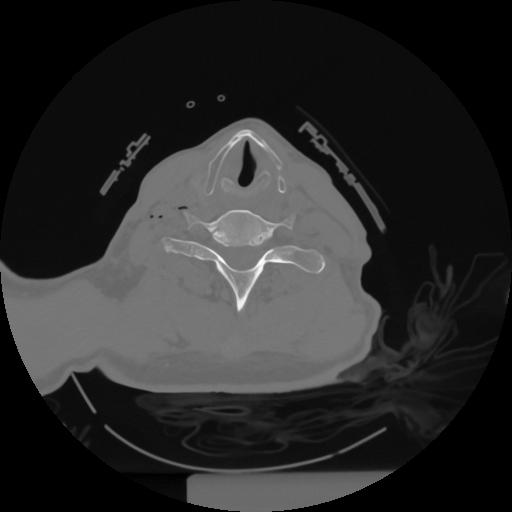

12 P.BLANDAS,,Vol,0.5,P.BLANDAS,,